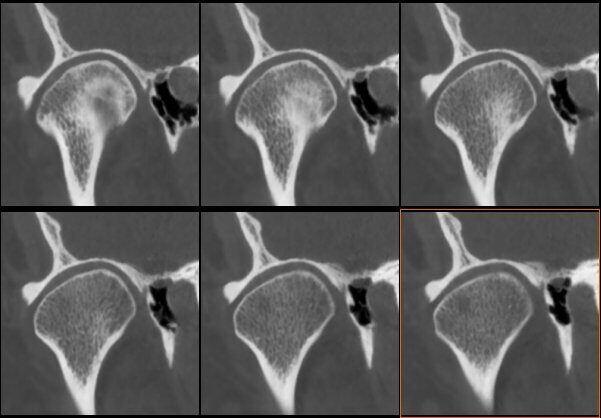

ATM Bocca Chiusa